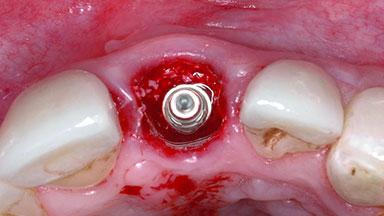

Replacement of a Failing Upper Left Central Incisor: Immediate Placement of an RC Bone Level Implant and Provisionalization

A healthy 23-year-old female patient was referred for a consultation on replacing tooth 21 with an implant-supported restoration. The patient had recently moved to the area and reported a history of endodontic and periodontal treatment for tooth 21. The tooth had been deemed non-restorable by her previous periodontist but since she was going to be moving, he recommended consulting to a dentist in her new city to continue her treatment. A review of her medical history yielded no significant findings and no known drug allergies. The analysis of her smile revealed a medium to high symmetrical smile line and a slightly discolored tooth 21.